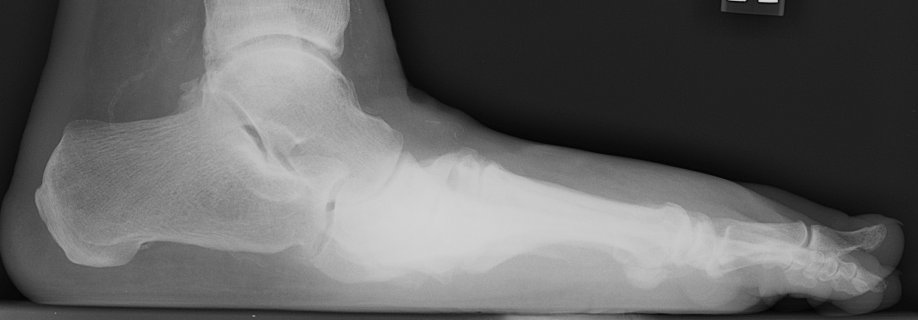

Return to Charcot Joint